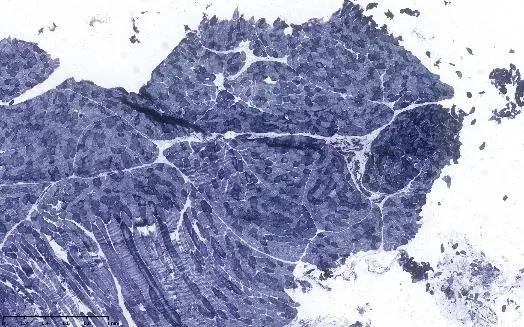

左侧腓肠肌活检:高倍镜下:显示肌束膜水肿伴炎细胞浸润;NADH酶组织染色,显示虫噬现象

王誉萱博士(病理科)点评:

低倍镜下可见肌纤维较一致,无淋巴组织浸润、纤维组织增生;但高倍镜下可见少量肌束膜水肿伴炎细胞浸润,肌纤维坏死萎缩,个别肌纤维束内镶边空泡改变,但对于诊断无特异性价值。NADH酶组织染色可见虫噬现象,SDH和COX染色未见线粒体肌病特征性改变。活检组织大体可见病变轻微,未见典型炎性肌病、代谢性肌病、线粒体肌病改变,不排除遗传性肌病或结缔组织病相关较轻的肌肉病变。